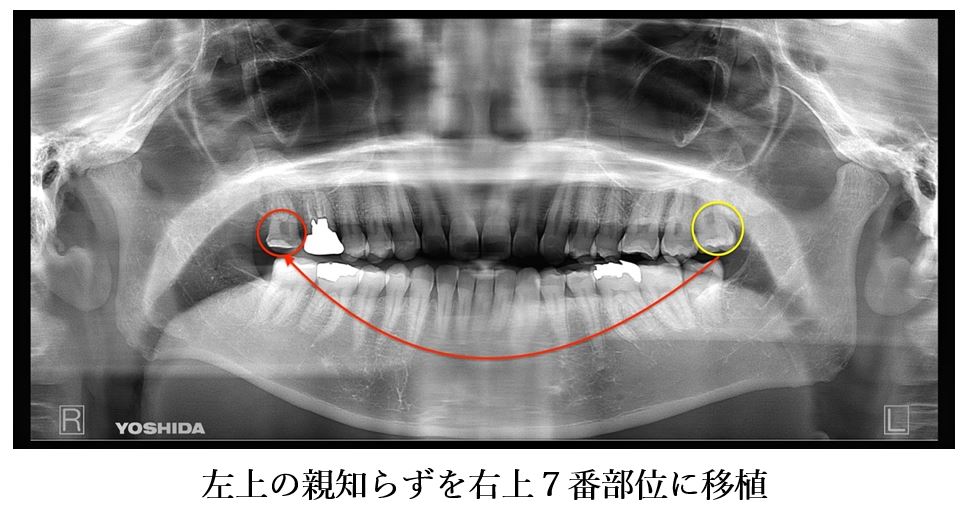

患者様はインプラントを行うことには抵抗があり、抜歯後のプランに左上の親知らずを右上7番部位に移植することを選択されました。

左上の親知らずを抜歯後、すぐに右上7番部位に移植を施し2週間経過後に精密根管治療を行いました。

本症例では幸運なことに左上の親知らずが健在していたため、口腔外科医と歯内療法専門医との連携により歯牙移植を行うこととしました。